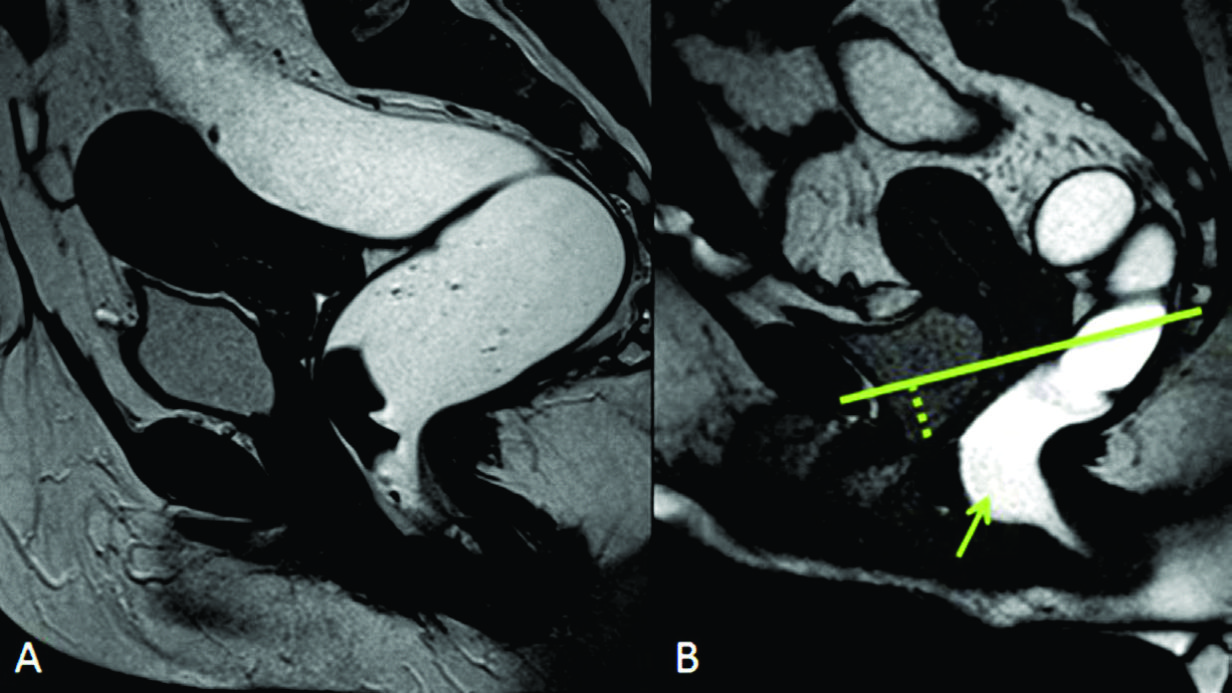

Figura 6

Cistocele,

pequeño rectocele anterior y prolapso de la cúpula vaginal. Imágenes TRUE FISP de alta resolución en el plano sagital a nivel de la línea media de una mujer durante A) el reposo y durante B) la defecación. Prolapso de la cúpula vaginal (triangulo en b) y rectocele anterior (estrella en B). Las líneas punteadas en verde miden la severidad de los prolapsos.

Figura 7

Rectocele anterior y cistocele.

Imágenes TRUE FISP de alta resolución en el plano sagital a nivel de la línea media de una mujer durante A) el reposo y durante B) la defecación. En B se observa angulación caudal del plano del elevador (flecha naranja), rectocele anterior (triangulo) y cistocele con hipermotilidad uretral (punteado azul en B).